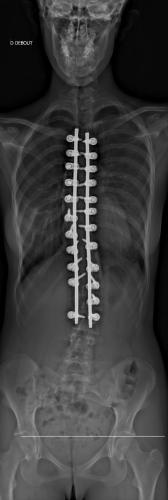

Images de scolioses opérées 16 janvier 202418 janvier 2023 par Damien Scoliose Thoracique et lombaire 1 Radio pré-opératoire de Face Radio pré-opératoire de Profil Radio à 1 an de recul de Face Radio à 1 an de recul de Profil